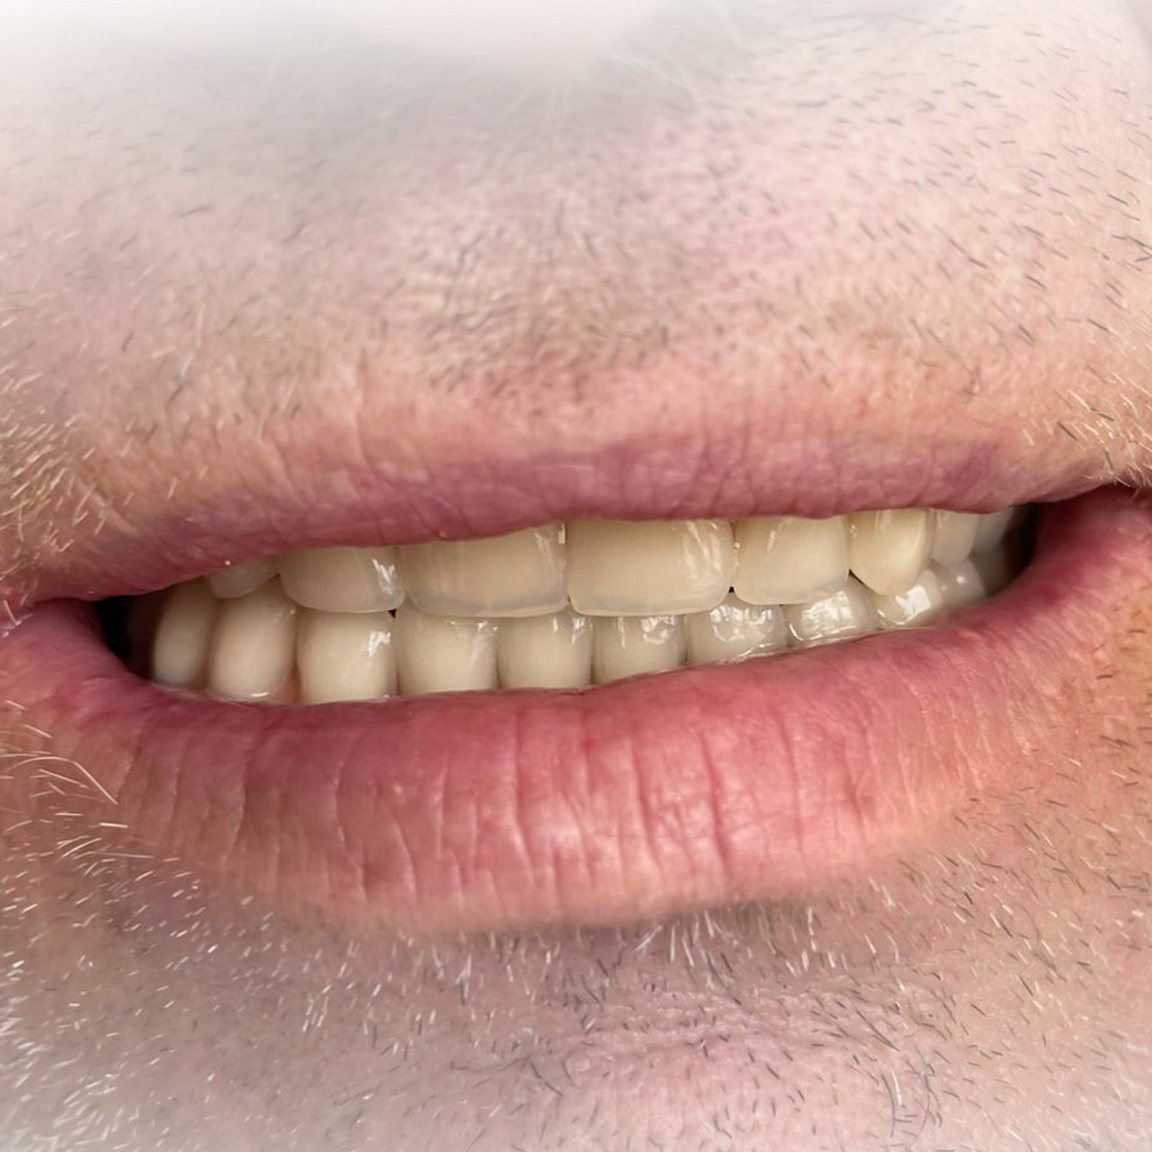

Ukázky naší práce

Branemarkův můstek s pryskyřičnými zuby

Branemarkův můstek se zirkonovými zuby